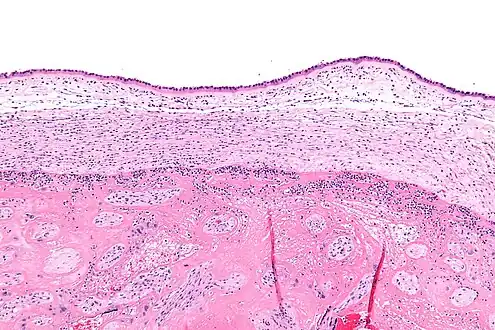

| Micrograph of acute chorioamnionitis, with neutrophils in the chorion. Also seen are fibrin clots, indicating a severe fetal inflammatory response.[1] H&E stain. | |

Infiltration of the chorionic plate by neutrophils is diagnostic of (mild) chorioamnionitis. More severe chorioamnionitis involves subamniotic tissue and may have fetal membrane necrosis and/or abscess formation.[1]